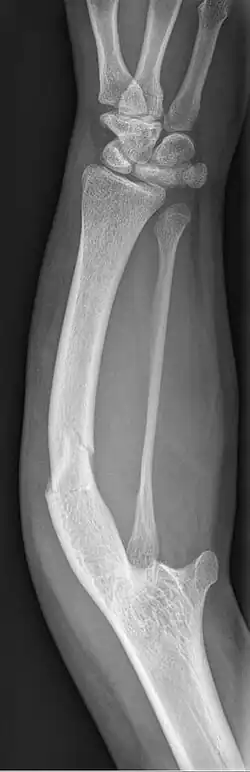

| Ulnar hypoplasia | |

Ulnar dysplasia also known as ulnar longitudinal deficiency, ulnar club hand or ulnar aplasia/hypoplasia is a rare congenital malformation which consists of an underdeveloped or missing ulnae bone, causing an ulnar deviation of the entire wrist. The muscles and nerves in the hand may be missing or unbalanced. In severe cases, ulnar digits (e.g. ring and pinky finger) may be missing. Sometimes, radial dysplasia occurs alongside this malformation.[2] This condition occurs in 1 in 100,000 live births.[3][4][5][6] Sometimes, other orthopedic problems occur alongside this malformation, such as scoliosis.[7]

Type 2: The ulnae is moderately-severely smaller than normal. The radius is deviated and so is the hand

Type 3: The ulnae is completely missing. The radius is even more deviated, causing a severe ulnar deviation of the hand.